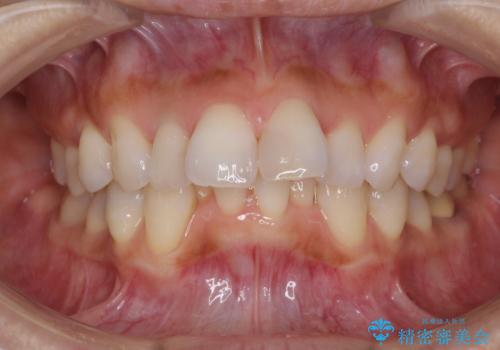

ワイヤーによる抜歯矯正でガタガタと深いかみ合わせの改善

- 上下の歯のがたつきを主訴に来院されました。

上下の前歯の叢生とかみ合わせが深い過蓋咬合という状態でした。

上下左右の歯を1本ずつ抜歯して、ワイヤーにて矯正を行いました。

かみ合わせの深さを改善するのに時間がかかり、予定よりも治療期間が長期化しましたが、整った歯並びへ改善することができました。